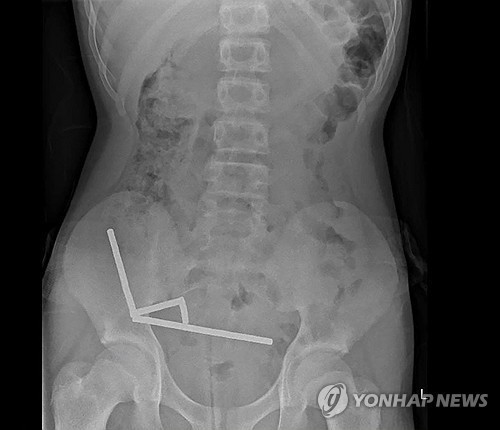

네오디뮴 자석은 지구상에서 가장 강력한 자석 중 하나로, 강력한 자기력으로 장내 조직을 압박해 손상을 유발할 수 있다. 실제로 엑스레이 검사 결과 소년의 장 내부에서 자석이 4개의 직선 형태로 뭉쳐 있었으며, 이로 인해 소장과 맹장에서 조직 괴사가 발생했다. 소년은 즉시 자석 제거와 손상된 장 조직 수술을 받아야 했다.